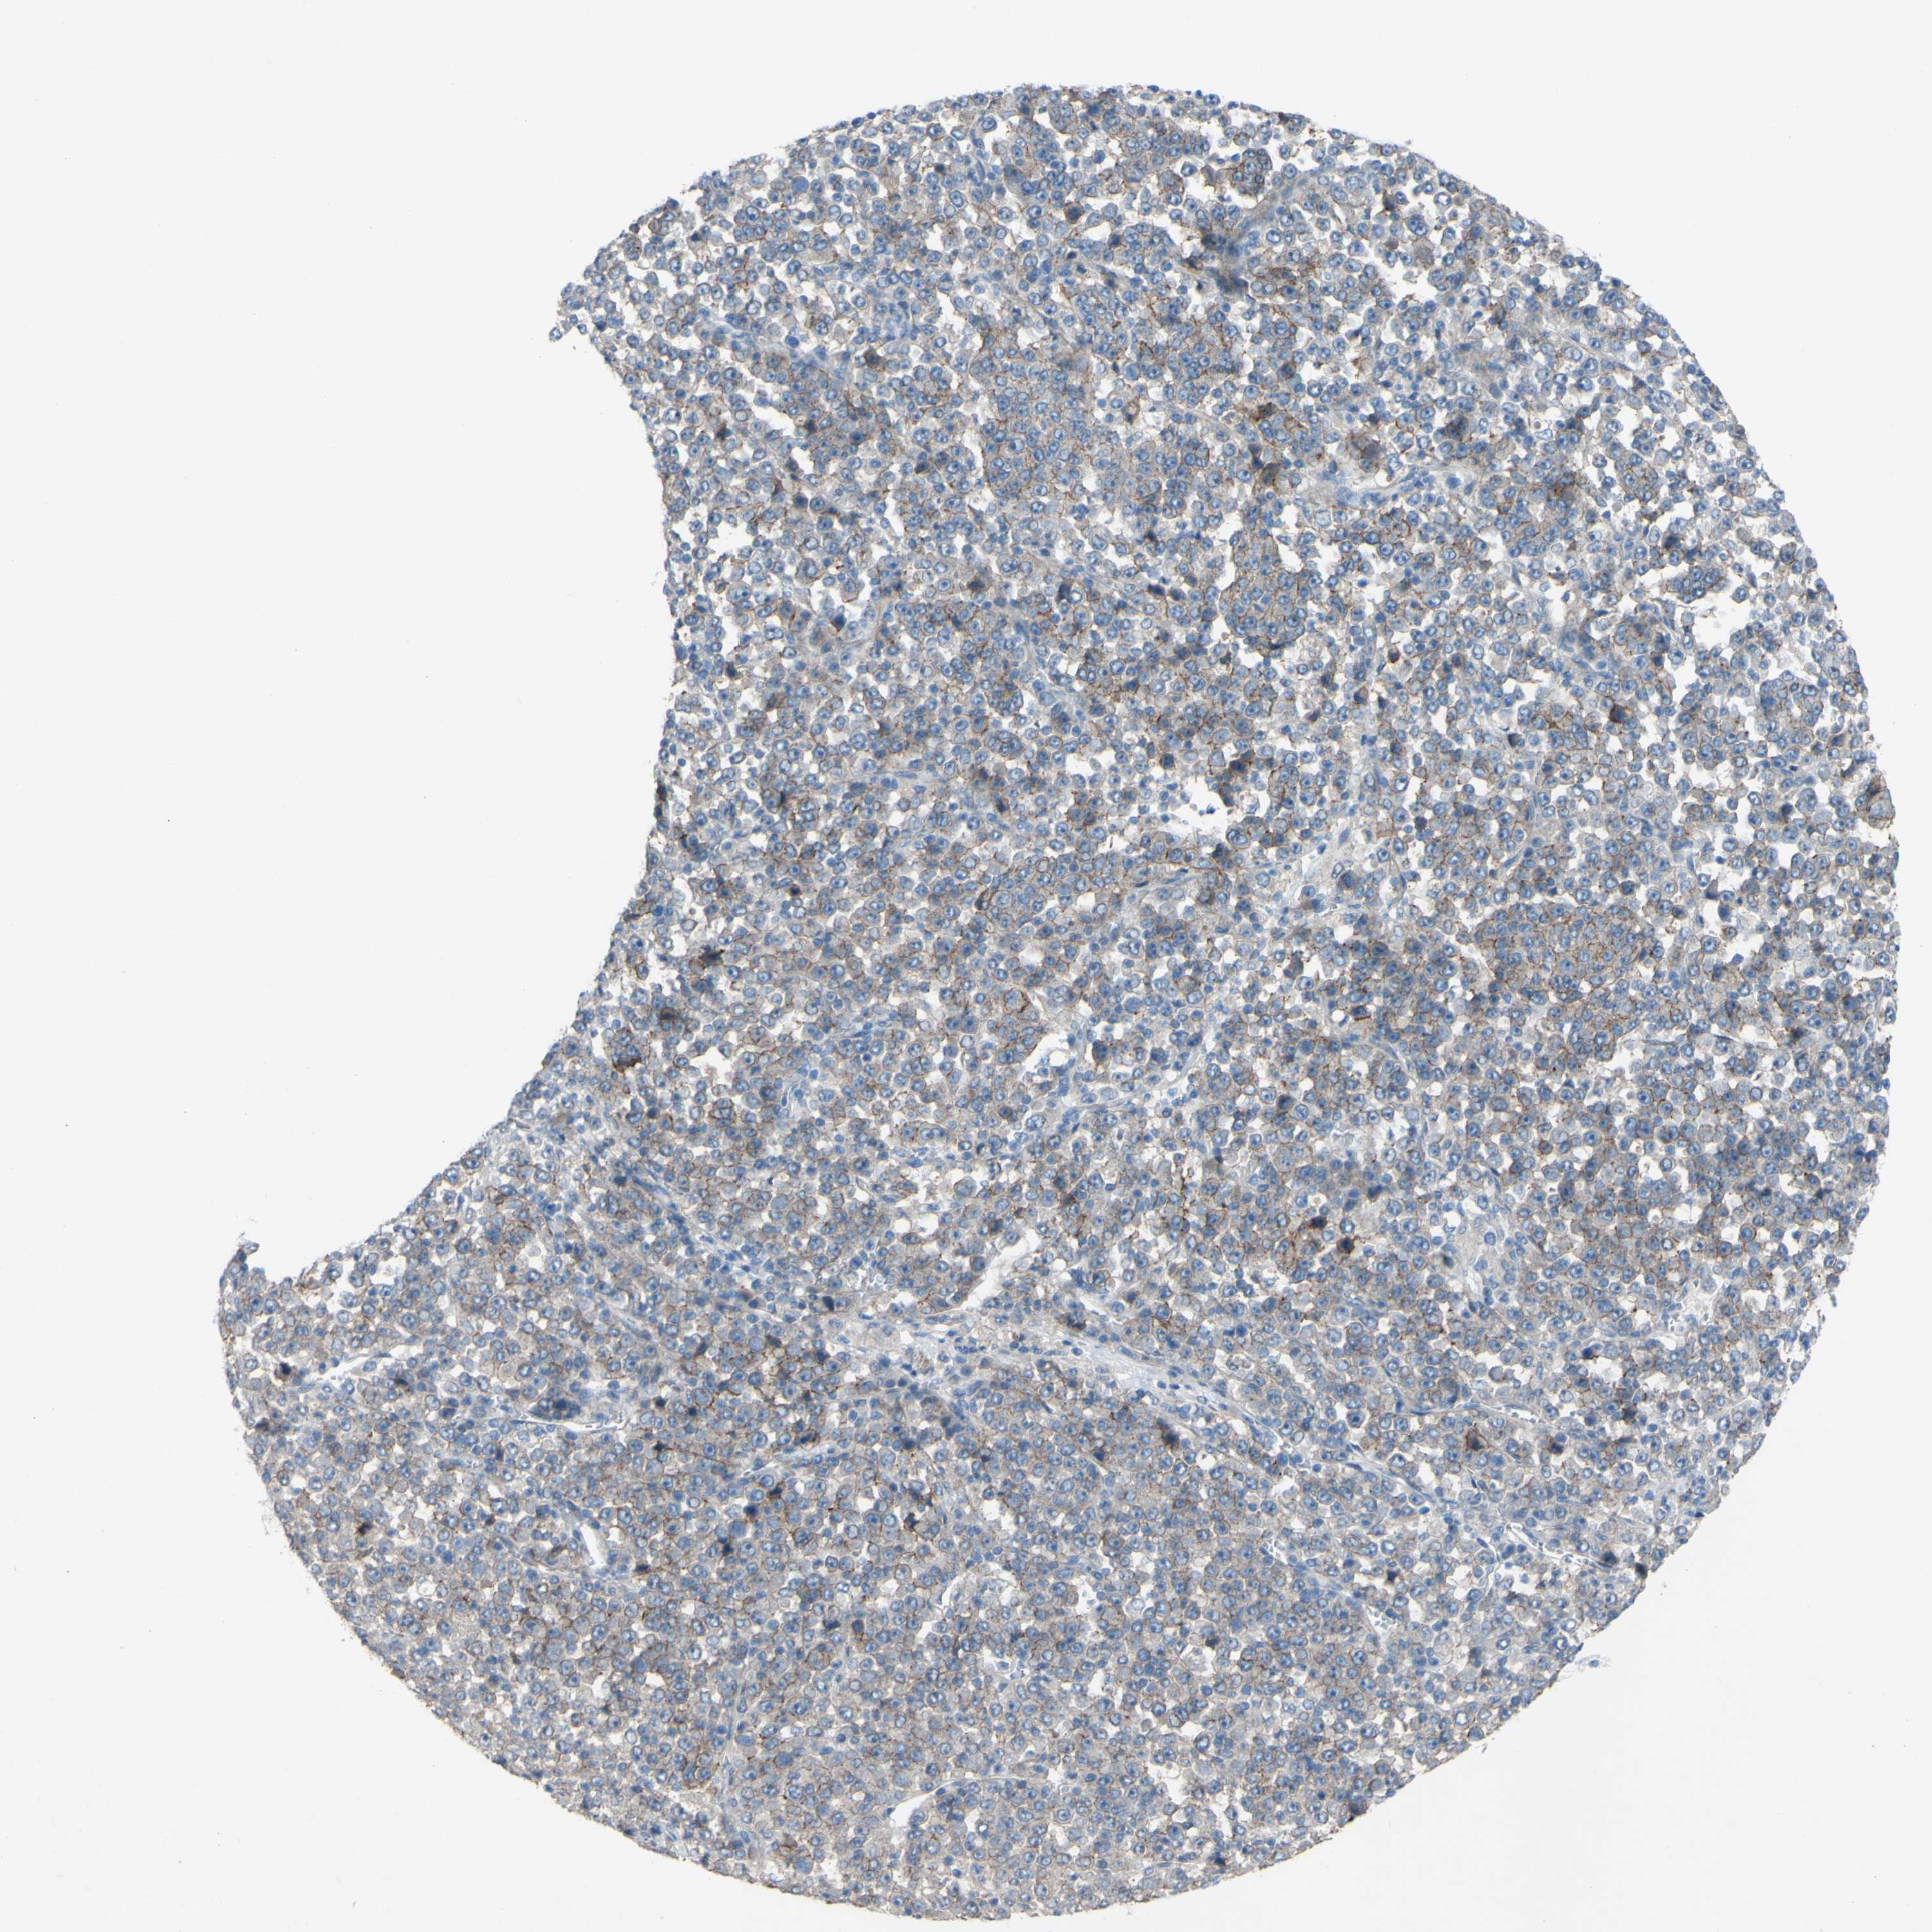

STOMACH CANCER - Protein expressioni

A mouse-over function shows sample information and annotation data. Click on an image to view it in a full screen mode. Samples can be filtered based on level of antibody staining by selecting one or several of the following categories: high, medium, low and not detected. The assay and annotation is described here.

Note that samples used for immunohistochemistry by the Human Protein Atlas do not correspond to samples in the TCGA dataset.

Antibody stainingi

Antibody staining in the annotated cell types in the current human tissue is reported as not detected, low, medium, or high, based on conventional immunohistochemistry profiling in selected tissues. This score is based on the combination of the staining intensity and fraction of stained cells.

Each image is clickable and will lead to virtual microscopy that enables deeper exploration of all samples and also displays staining intensity scores, fraction scores and subcellular localization as well as patient and tissue information for each sample.

Antibody HPA010978

Antibody HPA010979

Antibody CAB025637

Staining

High

Medium

Low

Not detected

Intensity

Strong

Moderate

Weak

Negative

Quantity

>75%

75%-25%

<25%

None

Location

Nuclear

Cytoplasmic/membranous

Cytoplasmic/membranous,nuclear

Adenocarcinoma, NOS

Adenocarcinoma, High grade